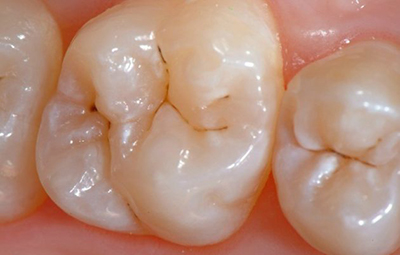

При появлении каверны усиливается чувствительность к изменению температурного режима, иногда — механического воздействия. Такие каверны, в просторечие называемые «дырками» в эмали, и становятся предметом беспокойства пациентов с больными зубами. В них начинает скапливаться еда, может появиться характерный неприятный запах.

При переходе кариеса в глубокую форму возникают кратковременные, резкие боли от разных видов воздействий. При устранении раздражителя они тоже стихают.

Внимание! Если после устранения раздражителя боль не исчезает, то воспаление пошло дальше, возможно, начался пульпит, а не просто кариес.

При появлении каверны проводится её санация различными способами удаления отмерших тканей. Затем производится пломбирование и выравнивание поверхности со шлифовкой.